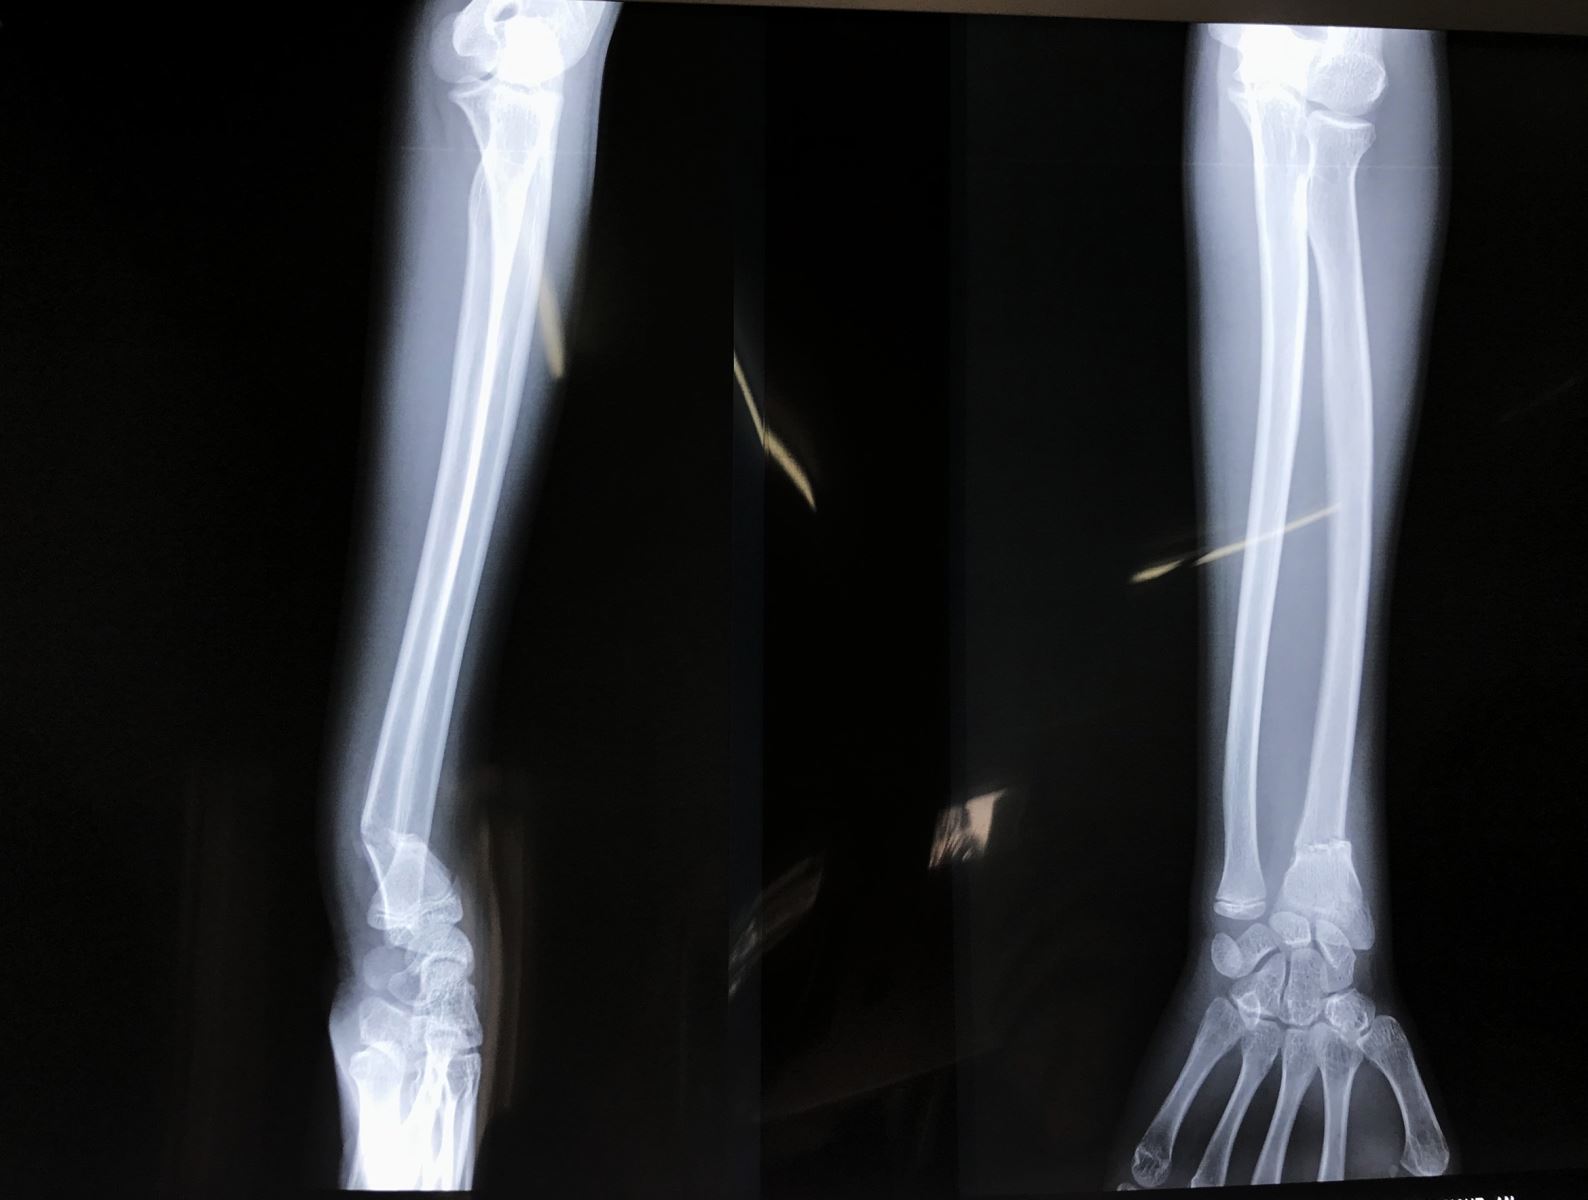

Chấn thương nhi: Gãy đầu dưới hai xương cẳng tay

Gãy đầu dưới hai xương cẳng tay ở trẻ em chiếm 20-36% các loại gãy xương trẻ em, trong đó 80% gãy hành xương, 20% bong sụn tiếp hợp. Độ tuổi thường gặp 8- 15 tuổi, nam thường gặp nhiều gấp 2-3 lần nữ

V. CHẨN ĐOÁN:

• X Quang cổ tay, cẳng tay thẳng nghiêng

X Quang khuỷu tay thẳng nghiêng nếu có đau về phía khuỷu hoặc có gãy thân xương